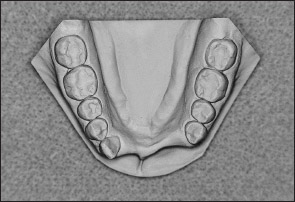

• Kennedy Class I arch: Characterized by bilateral edentulous areas located posterior to the remaining natural teeth (Figs 1-11 and 1-12).

Fig 1-12 Mandibular Kennedy Class I arch.